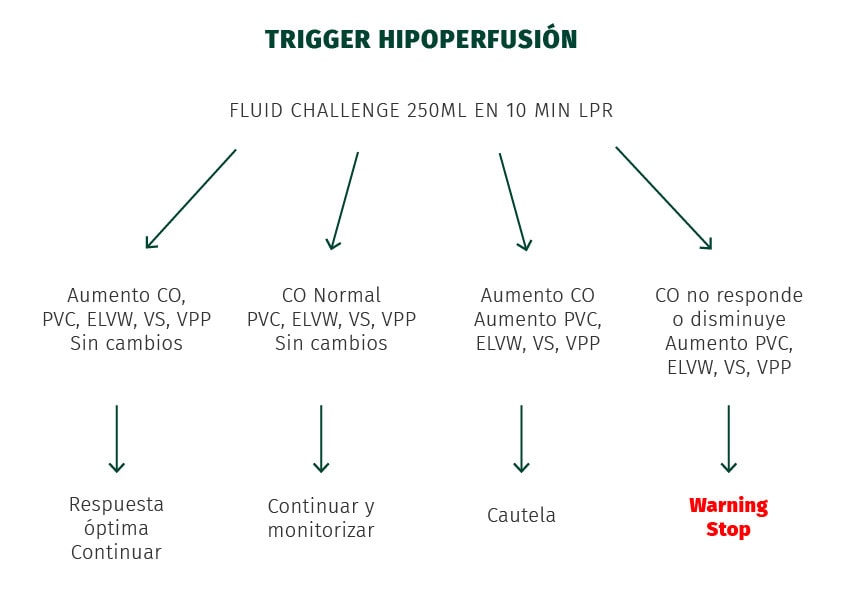

A la hora de detectar el trigger de la hipoperfusión, debemos fijarnos en los siguientes parámetros: CO, ELVW, VS, RCT y VPP.

El protocolo para la administración de fluidos sería el siguiente:

- Indicadores de respuesta a fluidos: identificar si es precarga-dependiente (responde a infusión de fluidos) para evitar complicaciones. Existen diversas técnicas como el test fluid challenge o la variación del volumen sistólico (VVS) y la variación de presión de pulso (PPV).

otros riesgos podrían ser isquemia mesentérica, el edema cerebral o las alteraciones de la oxigenación tisular. Por lo cual debe ser empleado el protocolo para la administración de fluidos El Trigger de Hipoperfusión

El protocolo para administración de fluidos que debe emplearse es el Trigger de Hipoperfusión